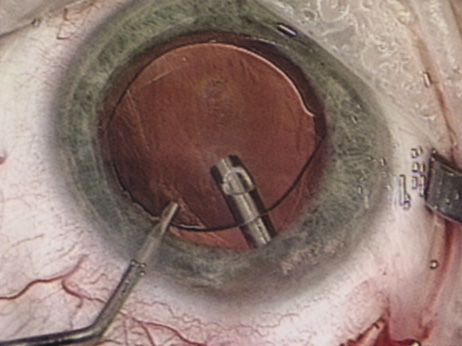

| There are many different approaches to disassembling the lens nucleus; each

level of experience. Slow-Motion Phacoemulsification Slow-motion phacoemulsification is a technique that seeks to maintain a stable anterior chamber during phacoemulsification while minimizing the volume of fluid that flows through the eye. By minimizing fluid inflow, there should be less endothelial cell loss and, therefore, less early postoperative corneal edema. Additionally, low inflow levels decrease the chance of forcing fluid through any areas of weakened zonules, which could create fluid lacunae within the vitreous gel, leading to positive pressure and possible vitreous prolapse. Chamber collapses are less likely because vacuum levels and aspiration rates are low; therefore, the risk of iris damage or posterior capsule rupture should be diminished. Because the technique involves low vacuum, aspiration, and inflow, it may be difficult to hold onto nuclear fragments for some methods of chopping the nucleus. Divide Techniques Divide techniques attempt to emulsify the nucleus by separating it into two or four pieces. Grooves carved into the nucleus facilitate separation of the pieces. The grooves can be achieved using low vacuum levels because complete occlusion of the phacoemulsification tip during is neither needed nor desired at this stage of the procedure. If one makes the groove at least twice the diameter of the phacoemulsification tip, there is better visualization of the walls of the groove, and thus better understanding of the groove's depth. A wide groove also results in the surgeon debulking more of the nucleus in the capsular bag, so that when the pieces are brought forward, less emulsification needs to be performed anteriorly. While fashioning the groove, it is important not to move the phacoemulsification tip faster than it is emulsifying. Advancing the tip too quickly causes the entire nucleus to move with the tip and may lead to subincisional zonular damage. The groove depth required to allow cracking depends on the density of the central and posterior nucleus. A hard nucleus with a dense posterior plate may not crack even if grooved through 90% of its thickness. Likewise, a fetal nuclear cataract may be cracked easily after grooving only halfway through. Regardless of the depth of the groove, the surgeon should place the cracking instruments at the most posterior aspect of the groove before dividing. (Fig. 17). Doing so minimizes stress on the anterior capsulorrhexis and generates forces more likely to result in a successful divide. After the nucleus has been bisected, the surgeon can debulk and emulsify each heminucleus separately. Alternatively, the surgeon can rotate the nucleus 90 degrees and further divide it into quarters in a similar fashion. After the surgeon has completed the divide portion of the procedure, vacuum and aspiration levels can be increased. By increasing vacuum and aspiration levels, the surgeon will find it easier to bring nuclear pieces to the phacoemulsification port. Additionally, higher vacuum levels hold the nuclear segments more tightly to the phacoemulsification port, resulting in more efficient phacoemulsification and better control. ”Chop” Techniques In 1993, Kunihiro Nagahara introduced a method of chopping the nucleus into pie slice–shaped wedges for emulsification (Fig. 18). Chopping techniques can be defined as vertical or horizontal chopping. Both chopping techniques involve burying the phacoemulsification tip into the center of the nucleus, holding it in place with increased vacuum. When performing a vertical chop, the chopping instrument is inserted through a second incision and placed beneath the anterior capsular rim. The chopper is directed peripherally, and then drawn posteriorly and centrally toward the phacoemulsification tip, causing the nucleus to crack. The horizontal chop differs in that the chopper does not need to be placed under the anterior capsular rim and the chop does not begin at the lens periphery. Instead, the chopping instrument is placed in the nucleus near the anterior capsulorrhexis edge and then directed posteriorly until it meets the buried phaco tip. Both chopping techniques take advantage of the natural cleavage planes between the nuclear lens fibers, similar to chopping a piece of wood with an ax. Each wedge can be brought centrally using a second instrument or the vacuum of the phacoemulsification tip for emulsification away from the posterior capsule, iris, capsulorrhexis edge, and bag periphery. Then the nucleus is rotated and similar maneuvers are performed with each segment until the entire nucleus has been emulsified. Smaller, more manageable wedges can be chopped off the nucleus for dense nuclei and larger pieces sectioned from softer nuclei.